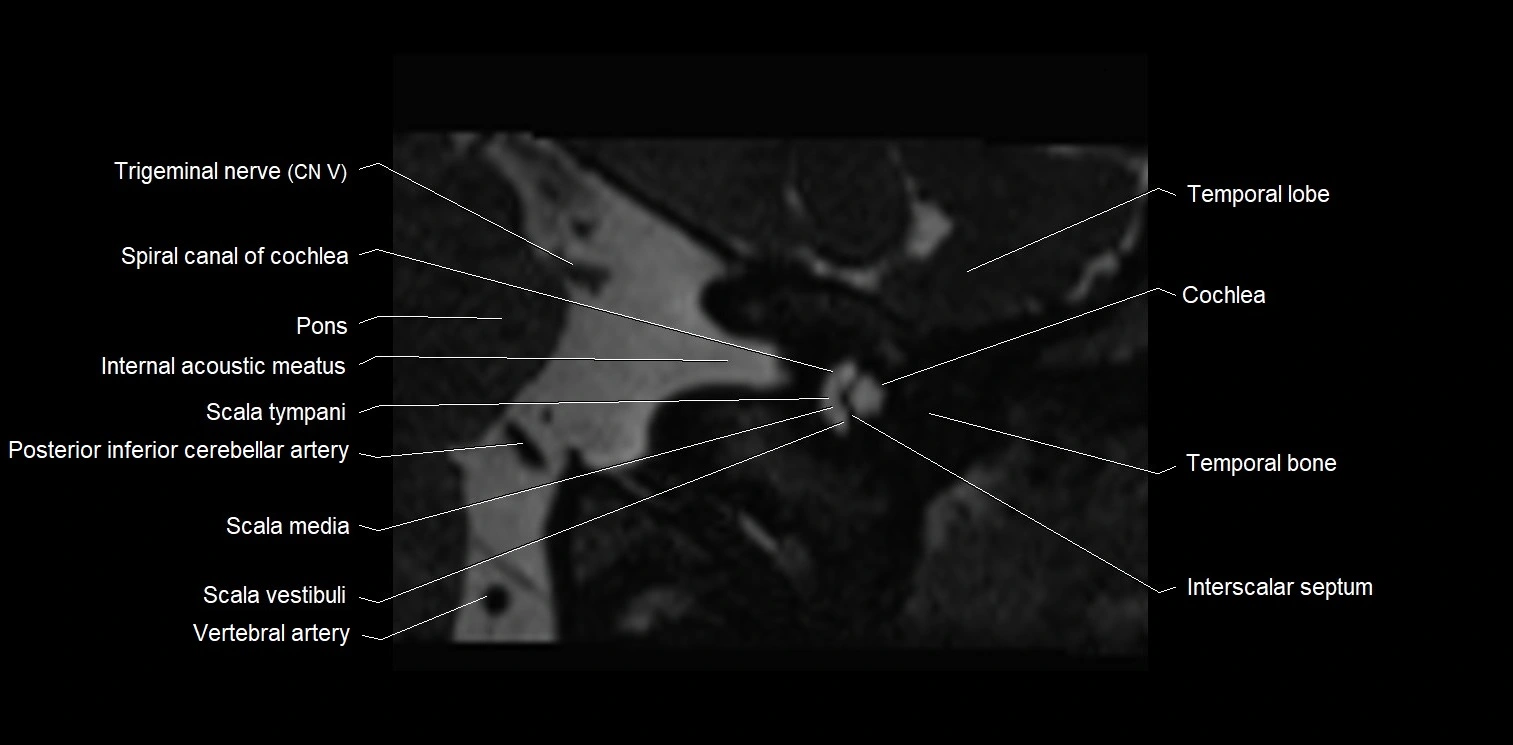

MRI images

image